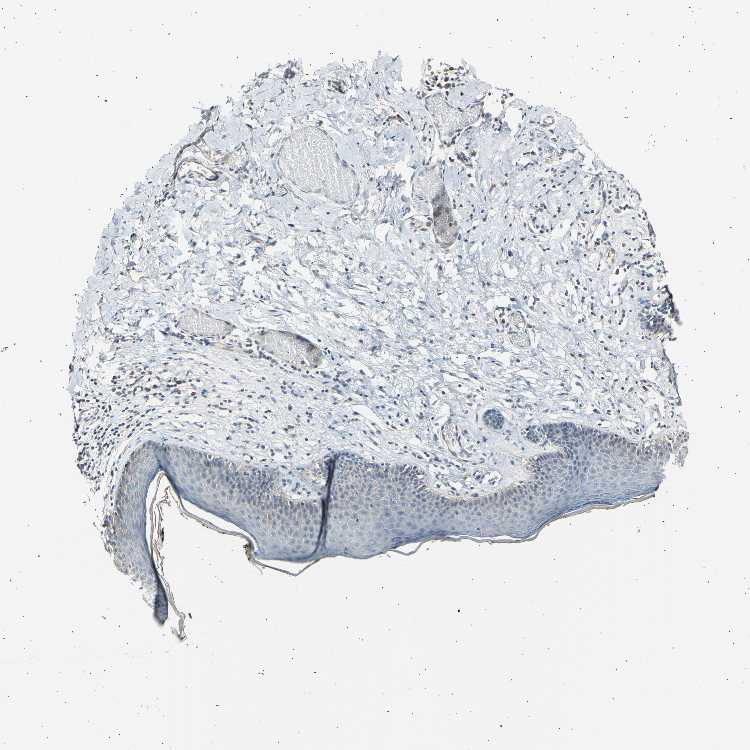

Tissue expression of LDLR Staining in vagina The Human Protein Atlas Protein Atlas Ldlr  The structure section provides predicted structures from the alphafold protein structure database and includes. If you continue, we'll assume that you. Low density lipoprotein receptor (hgnc symbol) entrez gene summary: The pathology section contains mrna and protein expression data from 17 different forms of human cancer. Correlation analysis based on mrna. Cytoplasmic expression in a subset of cells including cells. Protein Atlas Ldlr.

From www.proteinatlas.org